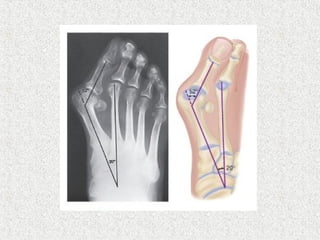

HALLUX VALGUS ANGLE

Normal <15

Mild <20

Moderate 20-40

Severe >40

1st

/2nd

Inter Metatarsal Angle (IMA)

Normal <9

Mild <11

Moderate 11-16

Severe >16

CLASSIFICATION NORMAL MILD MODERATE SEVERE

HALLUX VALGUS ANGLE < 15* < 20° 20° to 40° > 40°

1-2 INTERMETATARSAL

ANGLE

< 9* 11° or less. 12 - 15° 16° or more

SUBLUXATION OF THE

LATERAL

SESAMOID, AS MEASURED

ON AN AP RADIOGRAPH

Nil or

minimal

< 50% 50% to 75% > 75%

Classification